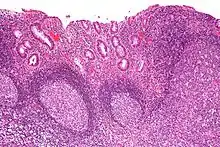

Micrograph showing colonic-type mucosa with follicular lymphoid hyperplasia, as is seen in diversion colitis. H&E stain.

Diversion colitis is an inflammation of the colon which can occur as a complication of ileostomy or colostomy, where symptoms may occur between one month and three years following surgery.[1] It also occurs frequently in a neovagina created by colovaginoplasty, with varying delay after the original procedure.[2] Despite the presence of a variable degree of inflammation the most suggestive histological feature remains the prominent lymphoid aggregates.